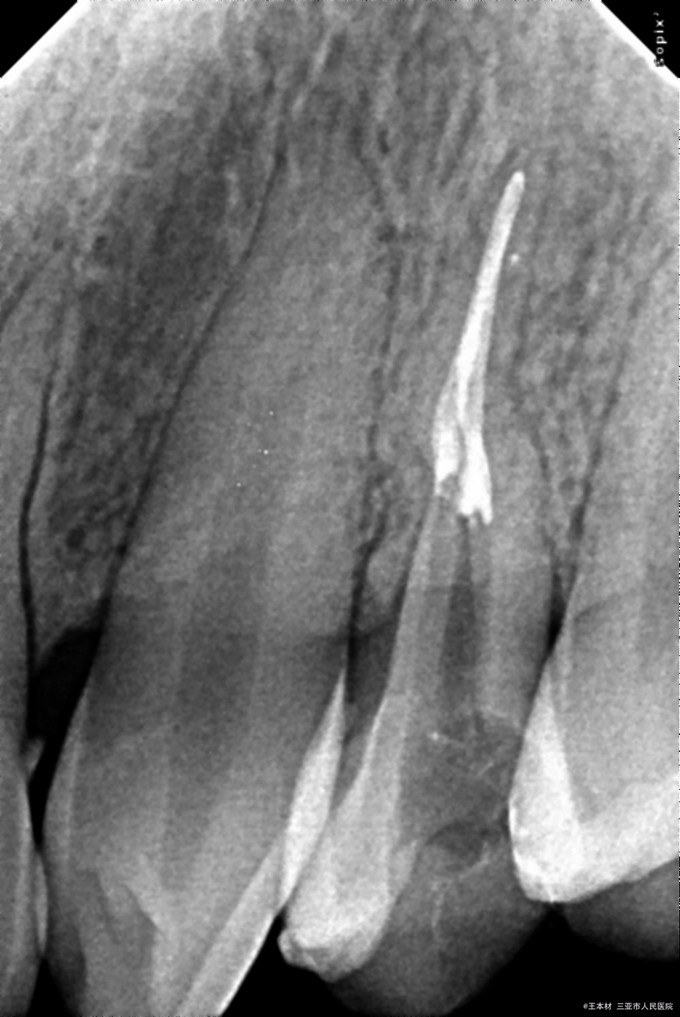

诊断:24#急性牙髓炎 处置:24#调咬合,去暂封,取失活,去净腐质,髓室预备,暴露髓室底,根管口探查,GG钻(1-3#)扩大根管口,拔髓,根管探查疏通,根管预备至:PWL=16.0,40#,根尖定位仪根管长度测量,WL=B:19.5mm,P:19.0mm,均35#,参照点为平各自牙尖,EDTA凝胶,0.7%NaClO冲洗,棉捻干燥,CP棉球,ZOE简单充填。 医嘱:全身抗炎阿莫西林,治疗其间勿用患侧咀嚼硬物,5日后复诊,不适随诊。 5日后复诊如下: 主诉:患牙无明显异常。 检查:24#封物完好,髓室内清洁,叩诊叩痛(-),棉球无异味,余无明显异常。 处置:24#去暂封,取棉球,NaClO冲洗,棉捻干燥,牙胶尖+氢氧化钙碘仿糊剂根管充填,玻璃纤维桩,3MZ350树脂修行充填。 医嘱:2小时后使用患侧进食,择期冠修复,随诊。

随访:患者失联。 讨论:此病例,患者年纪较轻,根管影像清晰、无钙化,根管较宽敞,因此根管阻力主要来自于弯曲。 操作细节: 1、在根管长度测量之前扩大根管口以及根管上段,减少根管冠方阻力——就笔者而言,这是常规操作——同时,在此病例中,将冠部弯曲进行初步处理。 2、根管锉预弯技术是探查弯曲根管的必要手段,微压力状态下将根管锉旋转“送入”根管弯曲内小段,确定临时工作长度PWL。 3、“就地预备”至40#,为了避免形成台阶,对于狭窄根管可采取非正规的“逐步后退”,既,在PWL的初尖锉确定后,每增大一号,减少少量工作长度,具体情况视根管内阻力而定。此病例根管较宽大,因此没有逐步后退预备PWL。此步骤完成后,S形根管变成了普通弯曲。 4、操作过程中伴随EDTA凝胶,可以起到润滑、化学预备,以及溶解碎屑、避免碎屑挤压至根管下段的作用。 5、每一阶段完成后,大量冲洗,但不是在每次更换器械的时候冲洗。EDTA与次氯酸钠之间有中和反应,降低了各自的作用,个人建议,仅供参考。 6、个人认为,将治疗难度降低,是解决根管探查及预备、充填过程中的核心理念。就如同篮球运动,将篮球传切至“空位”、“近篮筐”时,是提高命中率的有效办法——库里除外。 附注:CP棉球的根管封药时间也在一点点的缩短,现在笔者的CP封药时间在2~3日。